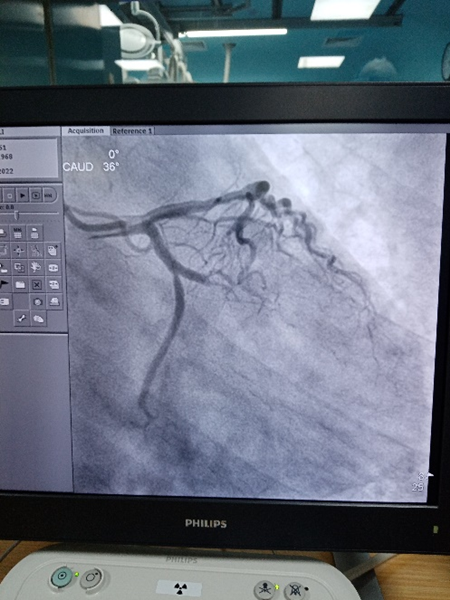

17时30分,患者到达医院,迅速按照预定路线快速送入介入手术室。消毒、铺巾、穿刺、造影。“回旋支堵了!”“来,上EBU导管”“上三件套”“上导丝”,高教授的话音落下,手术室内就显的有些安静了,能清晰听见的声音只有大家忙碌的脚步声和压力泵撤回的“啪啪”声,“导丝过去了,来球囊扩一下……”“好,小范造个影!”“好粗的回旋支啊,上支架!”“上后扩球囊”。在场的所有人员都为患者捏了一把汗。

18时05分,随着压力泵最后“啪”的一声,支架完美的贴靠在了回旋支闭塞的血管病变处,造影剂“划出了”一道靓丽的“风景线”!患者胸闷,胸痛症状明显缓解,生命体征恢复稳定。在场的团队成员舒缓了紧张的心情,患者得救了!